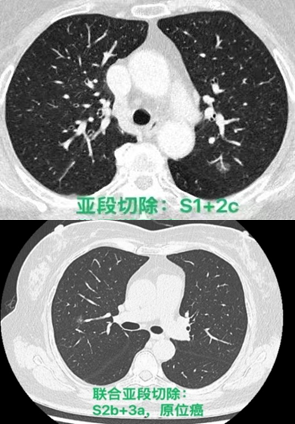

常规腔镜方面,以胸部肿瘤外科为主,开展肺叶、肺段、复合肺段/亚段切除、解剖性肺切除、袖状切除等手术,包括单孔到多孔等各种入路。在北京市较早开展微创食管癌切除,积累了丰富的经验。纵隔肿瘤方面,开展包括剑突下及其他入路胸腺切除、胸腺扩大切除,无名静脉成型等。同时结合锚丝定位、术前三维重建技术和荧光腔镜技术使手术安全高效。

目前主流的胸外科微创手术业务我科已达到全覆盖。包括但不限于:胸腔镜下肺叶、肺段、亚段、联合亚段、全肺、肺袖状切除术;单孔胸腔镜微创手术,Hook-Wire定位小结节精准切除手术,微创胸腹腔镜联合食管癌切除术,剑突下纵隔肿物切除术,达芬奇机器人辅助各类手术等几乎所有的胸外科先进微创的手术方式。